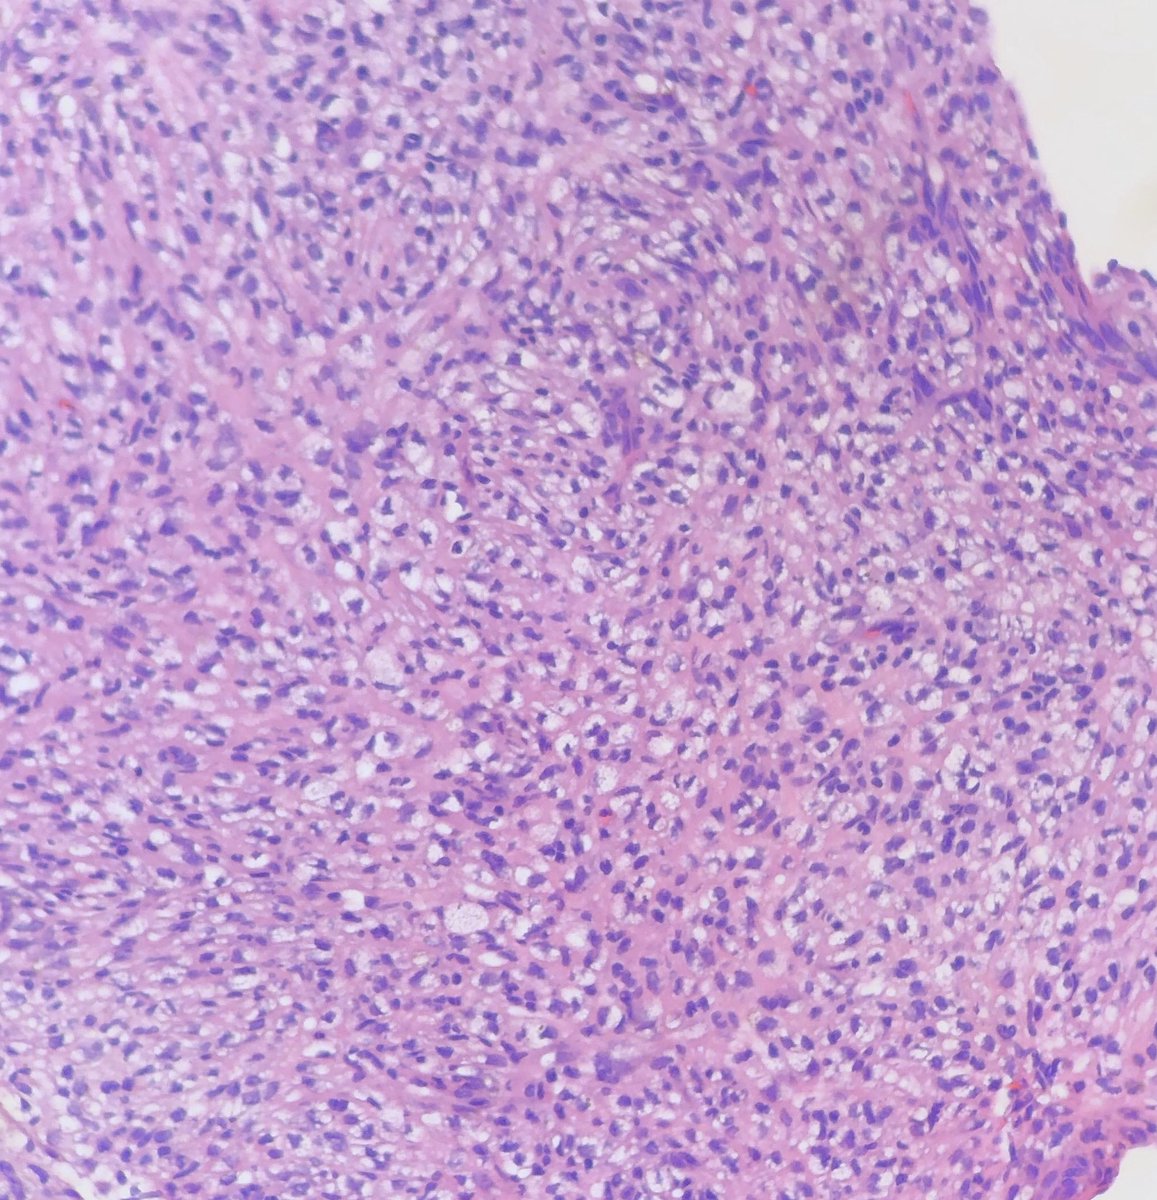

@StanfordPath Saturday!

50 YO man with nodules in the duodenum

Expansion of lamina propria and submucosa with follicular structures of small lymphocytes with centrocyte morphology

See IHC photos below

t(14;18) IGH/BCL2

#stanfordpathsaturday#meded#pathologytwitter pic.twitter.com/iKF8tpqM8A